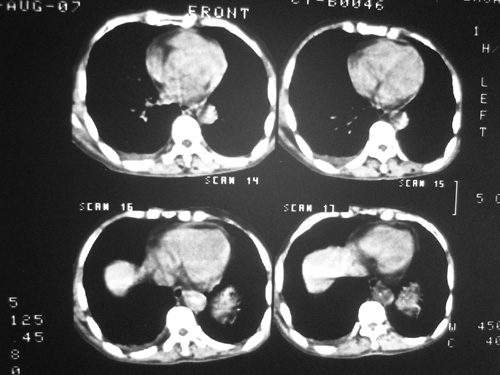

老年男性,70岁。煤矿工人20年。一周前咳嗽、发烧,拍x片考虑矽肺可能。始终咳嗽行ct检查,发现弥漫性病变,似感染但密度很高,细支气管肺泡癌无法排除,请老师给予指点。

一般矽肺多为双肺融合状,团块状高密度结节影.并散在多处小结节影.可这个病人只表现在单肺,并没有融合结节影.一周前的x片没显示大片高密度影,可定位扫描时(图象忽略传了),右肺已经清晰显示大片高密度影.作比较感觉是新病灶.可实际表现又不象,所以才拿来让各位老师看看.